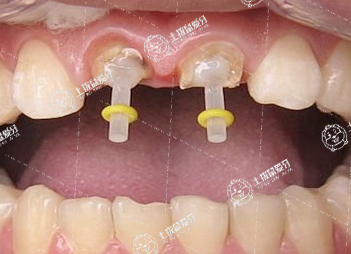

種牙是將人工種植體安裝到牙槽骨內(nèi),人工種植體與牙槽骨骨結(jié)合穩(wěn)定后,將人工牙冠通過(guò)基臺(tái)安裝到人工種植體上,可以使牙齒行使咀嚼功能,鑲牙需要以鄰牙作為基牙,將鄰牙磨小一部分,把做好的牙冠安裝粘接到鄰牙上,行使咀嚼功能。

2.種牙則是種植牙的簡(jiǎn)稱,是指通過(guò)手術(shù)的方式在牙床上植入與人體兼容性高的金屬,經(jīng)過(guò)1到3個(gè)月金屬與牙床緊密結(jié)合后再將人工烤齒牙冠安裝在金屬牙根上;優(yōu)點(diǎn)是穩(wěn)固、咀嚼效果好、舒適;但同時(shí)也應(yīng)避免咀嚼過(guò)硬的食物,定期到醫(yī)院進(jìn)行維護(hù)。

1.種植牙屬于目前牙體缺失最先進(jìn)的一種修復(fù)方式,是通過(guò)在缺隙處植入種植體的方法完成修復(fù),固位在牙槽骨上固位力強(qiáng),不損傷兩側(cè)牙體組織,但會(huì)暫時(shí)性在種植區(qū)域留下創(chuàng)口,修復(fù)時(shí)間一般在半年左右,種植費(fèi)用昂貴。